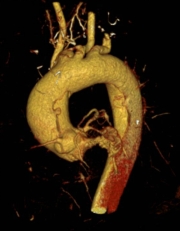

一切准备就绪后,手术团队为第一位患者实施了“主动脉根部成形+升主动脉置换+全弓置换+弓上三分支重建+远端支架植入术”。该手术属心外科领域最复杂、技术要求最高的术式之一,需在深低温停循环的有限时间窗内,精准重建心脏输出的“生命主干道”。手术历时5个多小时顺利完成,患者术后恢复良好,已康复出院。

后续,手术团队为另一位患者实施了技术难度更高的“主动脉根部成形+主动脉瓣成形+升主动脉置换+全弓置换+弓上三分支重建+远端支架植入术”。该手术在置换病变血管的同时,成功修复了患者自身的主动脉瓣,既清除了致命隐患,也避免了术后终身抗凝,显著提升了患者的远期生活质量。该患者术后转入ICU监护,病情稳定后现已转回普通病房继续治疗。

常规二尖瓣主动脉瓣膜置换,瓣膜成形修复,主动脉夹层A型手术(升主动脉置换+全主动脉弓人工血管置换+橡皮支架植入)、B型夹层腔内隔绝术、保留主动脉瓣的主动脉根部置换术(David I)、主动脉瓣置换伴升主动脉置换术(Wheat's)、Bentall、 On/Off-bump冠状动脉旁路移植、肥厚型梗阻性心肌病改良morrow手术、胸腔镜左心耳夹闭术、心房颤动经胸/胸腔镜心脏射频消融改良迷宫手术等。